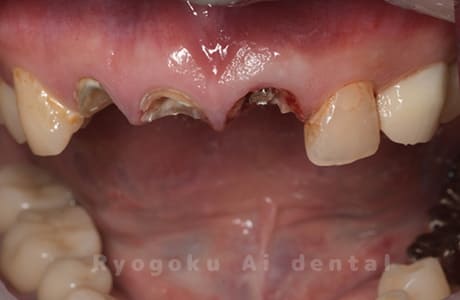

Case02

-

- 原因

- 重度縁下カリエス、慢性根尖性歯周炎

- 治療期間

- 約3ヶ月(最終補綴装着まで含む)

- 治療内容

- クラウンレングスニング+歯周外科+マイクロエンド

- 治療費用

- 165,000円(最終補綴を除く)

他院で抜歯を宣告された患者様です。歯の根の治療(マイクロエンド)と歯周外科・クラウンレングスニングを行いました。

<リスク・副作用>

手術後は痛み、腫れ、痺れ、青あざなどの副作用が生じます。痛みは痛み止めを処方しますが、腫れ、青あざは1週間程度生じる場合があります。また、部位によっては神経の走行が複雑で、痺れが残り、長期的にお薬を処方する場合があります。